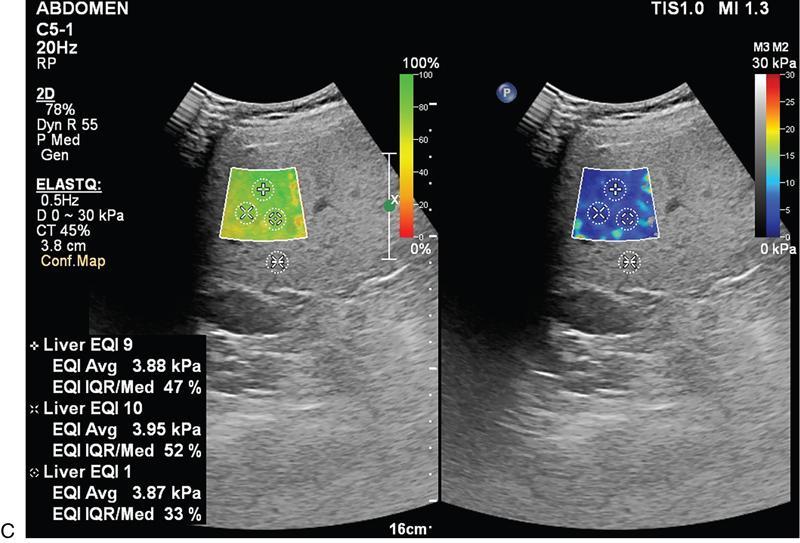

Liver elastography

Two main methods used are ARFI (acoustic radiation force impulse) and fibroscan

Technique

Scoring system

Liver Fibrosis Staging

Metavir Score

kPa

m/s

Normal

F0

2.0–4.5

0.81–1.22

Normal–Mild

F0–F1

4.5–5.7

1.22–1.37

Mild-Moderate

F2–F3

5.7–12.0

1.37–2.00

Moderate–severe

F3–F4

12.0–21.0+

2.00–2.64+